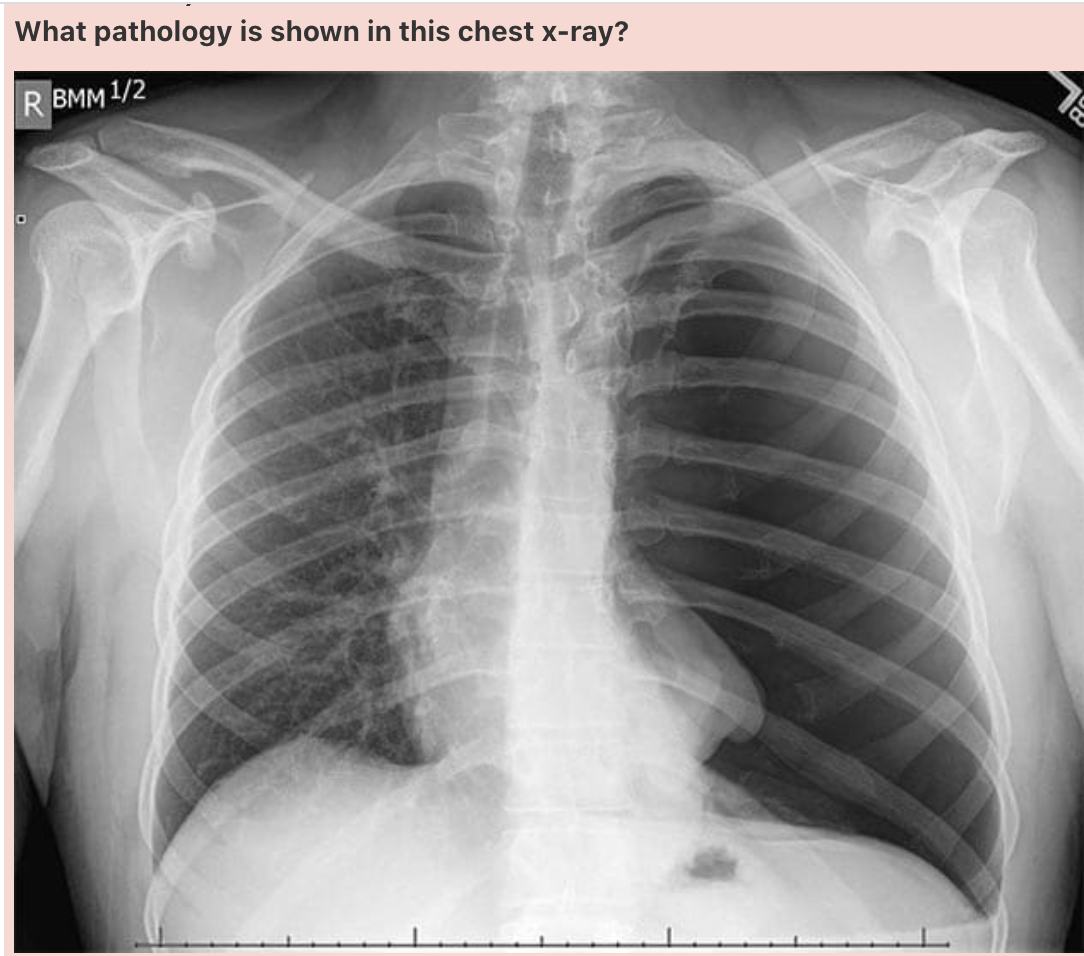

What pathology is shown in this chest x-ray?

Answer: Pulmonary oedema